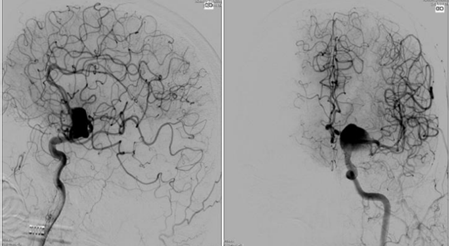

Exame de arteriografia cerebral com reconstrução tridimensional, melhor método de imagem para avaliação do aneurisma cerebral.

Para este procedimento, um neurorradiologista intervencionista realiza uma angiografia cerebral, idealmente com reconstrução 3D, para planejar o tratamento a ser realizado por via endovascular. Temos inúmeras técnicas para o tratamento, depende da localização, tamanho, morfologia, se já foi anteriormente tratado e do tamanho do colo “do pescoço do aneurisma”. Tais técnicas podem ser resumidas em 4: